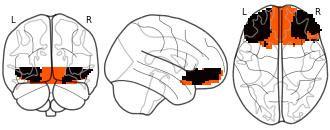

Connectivity-Based Parcellation of the Human Orbitofrontal Cortex: K=2...

EmailClick to copy linkLink copied Cite(2024). Connectivity-Based Parcellation of the Human Orbitofrontal Cortex: K=2 cluster map [Dataset]. http://identifiers.org/neurovault.image:887623niftiAvailable download formatsUnique identifierhttps://identifiers.org/neurovault.image:887623Dataset updatedNov 18, 2024License

Cite(2024). Connectivity-Based Parcellation of the Human Orbitofrontal Cortex: K=2 cluster map [Dataset]. http://identifiers.org/neurovault.image:887623niftiAvailable download formatsUnique identifierhttps://identifiers.org/neurovault.image:887623Dataset updatedNov 18, 2024LicenseCC0 1.0 Universal Public Domain Dedicationhttps://creativecommons.org/publicdomain/zero/1.0/

License information was derived automaticallyDescriptionK=2 cluster map based on N=13 participants.

Collection description

K-means cluster maps of orbitofrontal cortex with K=2, 3, 4, 5, 6, and 7 clusters based on resting-state fMRI data.